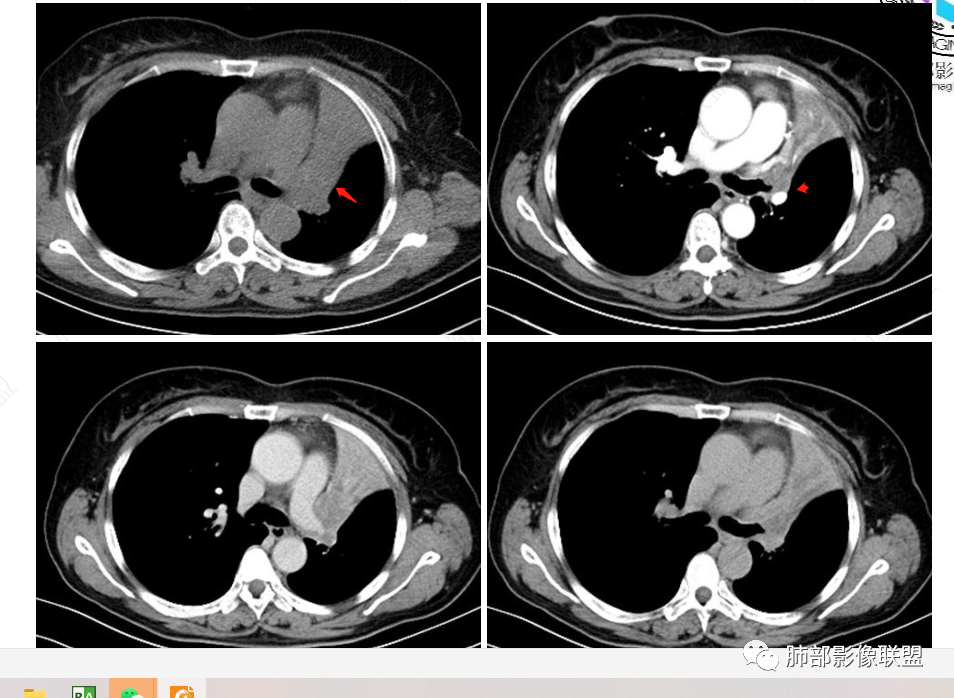

2、影像表现:正常肺背景,左肺上叶支气管腔内占位,上叶支气管截断,远端肺组织不张,强化差异衬托出肺门区结节影或块状影。增强扫描腔内占位轻中度不均匀强化,可见坏死,远端粘液栓,局部肺动脉受压、侵犯,纵膈淋巴结无明显肿大,无胸腔积液。

②腺样囊性癌、粘液表皮样癌属于涎腺肿瘤,多见于40-60岁人群,男女发病率无显著差异,与吸烟无关,发病部位前者以气管及主支气管多见,后者以叶段支气管多见,多表现为支气管腔内占位,强化程度较轻,二者影像表现相似,常常较难鉴别。

③类癌属于低度恶性神经内分泌肿瘤,发病年龄13-70岁,成年人中以中央型类癌多见,影像表现为支气管腔内的圆形或卵圆形结节,边缘光整,也可浅分叶,可完全位于支气管腔内,也可以病变管腔内的病变只占病变的一小部分,大部分位于管腔外,称为“冰山征”,少数病例可沿支气管腔内长轴生长,呈指套样改变,可伴有小部分位于腔外,类似部分鳞癌的表现,但类癌血供较鳞癌丰富,多数呈显著较均匀强化,不典型类癌可呈不均匀强化,肿块较大时可阻塞支气管导致肺不张。

④小细胞肺癌属于高度恶性神经内分泌肿瘤,好发于吸烟男性,多数小细胞癌影像表现较典型,表现为肺门旁或外周边缘膨隆、边界清楚的软组织结节或肿块,由于肿瘤组织坏死不彻底,常表现为“沼泽样”坏死区,较早出现肺门和纵膈淋巴结转移,有“娘小崽大”的特点。纵隔淋巴结融合,可形成“冰冻纵膈”。小细胞癌侵袭力强,容易包埋血管形成“血管包埋征”,肿瘤沿支气管浸润时可见病灶呈鸭蹼和腊肠样凸起,相较于鳞癌而言,小细胞癌导致的阻塞性肺炎常常较轻,较少合并肺不张,少见合并胸水。

就本例而言,患者为女性,无肺气肿背景,未提及吸烟史,影像上强化程度偏轻,未见湖泊样坏死,尽管中央型肺癌中以鳞癌最多见,且造成完全阻塞及肺不张,但在女性患者诊断鳞癌仍需谨慎。支气管腔内结节,强化程度轻,涎腺肿瘤需要考虑,不典型类癌也不能除外。女性患者,未提及吸烟史,尽管未见纵膈淋巴结明显肿大,但支气管明显相关,小细胞肺癌亦应当重点排除。